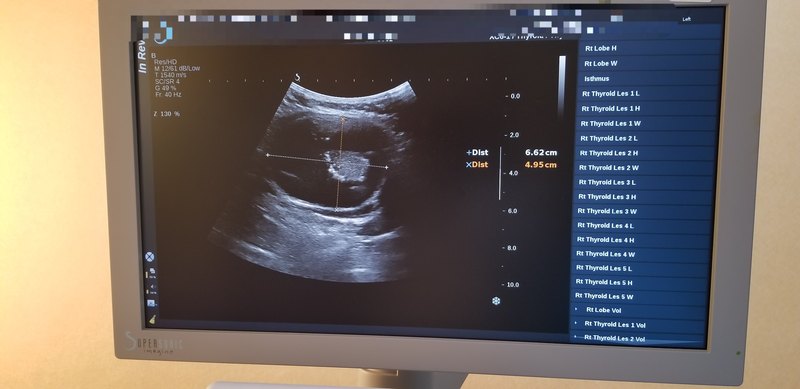

去年底一外地女性患者來(lái)我科就診,甲狀腺超聲檢查見(jiàn):右葉甲狀腺見(jiàn)一超大囊實(shí)性結(jié)節(jié),大小為:8.2*6.62*4.95cm 囊實(shí)混合回聲結(jié)節(jié),形態(tài)規(guī)整,邊界清晰。 患者自述該結(jié)節(jié)從兩個(gè)多厘米時(shí)就在看,每次醫(yī)生都告訴良性,不用處理?,F(xiàn)在長(zhǎng)到了8個(gè)多厘米。前些天去看病的醫(yī)院還告訴是良性?,F(xiàn)想處理,欲行超聲引導(dǎo)下的熱消融術(shù)。 此患者超聲顯示:雖是囊實(shí)性回聲,但實(shí)性部分表面欠規(guī)整,且可見(jiàn)點(diǎn)狀強(qiáng)回聲附著。彩色血流顯示:實(shí)性部分血供豐富??紤]為惡性可能性大。先行超聲引導(dǎo)下的FNA, 病理回報(bào):傾向甲狀腺乳頭狀癌。 囊實(shí)性結(jié)節(jié)通常被認(rèn)為是良性,但當(dāng)實(shí)性部分見(jiàn)以下特征:形態(tài)不規(guī)整;可見(jiàn)點(diǎn)狀強(qiáng)回聲;血流豐富;生長(zhǎng)較快等時(shí),不能除外惡性。